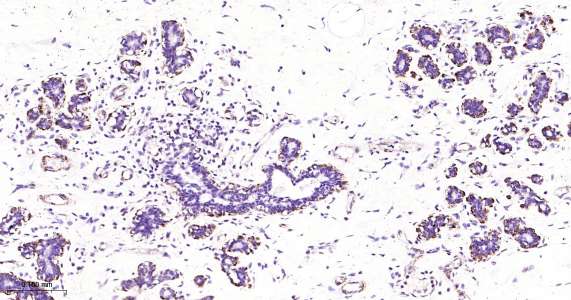

Immunohistochemical analysis of paraffin embedded mouse stomach tissue slide using IHC0473 (Vinculin IHC Kit).

Immunohistochemical analysis of paraffin embedded human mammary gland tissue slide using IHC0473 (Vinculin IHC Kit).

Immunohistochemical analysis of paraffin embedded rat colon tissue slide using IHC0473 (Vinculin IHC Kit).